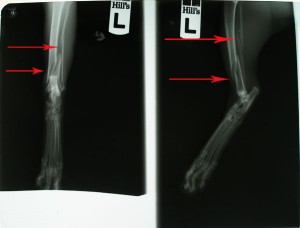

Po operaci obou kostí

kontrolní rentgen měsíc po operaci: 467,-Kč